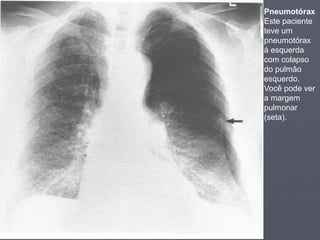

Pneumotórax

Este paciente

teve um

à esquerda

com colapso

do pulmão

esquerdo.

Você pode ver

a margem

pulmonar

(seta).